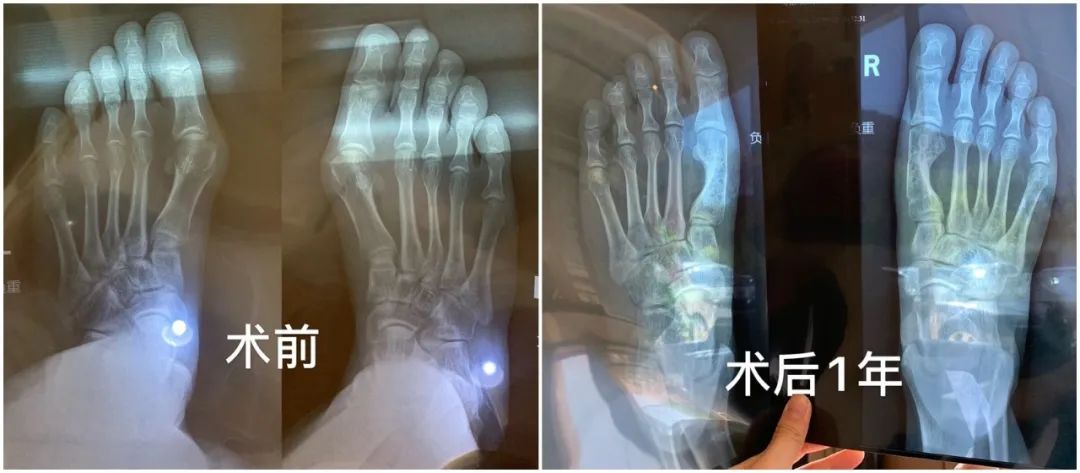

还有每次写高跟鞋都会有人烦恼的问题——拇指外翻。也有小伙伴去做了修复手术,来看看她的分享:

拇指外翻手术

👧🏻X

拇外翻手术

其实拇外翻是一种疾病,所以算是治疗手术,它是能够医保报销的!不算美容!

很多人以为拇外翻只是脚丑,我去年疼痛剧烈,甚至无法走路,立刻在网上找到一位非常合适的三甲医生立刻就做了。传统方式,断骨重接,并不是单纯切掉歪出来的那一块然后掰脚趾头!拇外翻一定不能做微创!一定不能!谁做谁后悔!

住院三天,术后能够脚后跟点地去厕所,卧床到下地一个月,三个月能够恢复剧烈运动。现在不疼不歪不丑,穿鞋美美的了!

医保前23000,医保后8700。我选择了可吸收钉,强度不如钛钉但没有内固定物,几年以后就被人体吸收没了。钛钉强度高,下地时间早,但总归是脚里有个钉子不是。

皮肤疤痕恢复时间因人而异了,有人3个月就看不到了,有人几年还有增生,但疤痕相对拇外翻的问题来说都是小问题了,疤痕在侧面,基本看不到。全部注意事项就是遵医嘱!